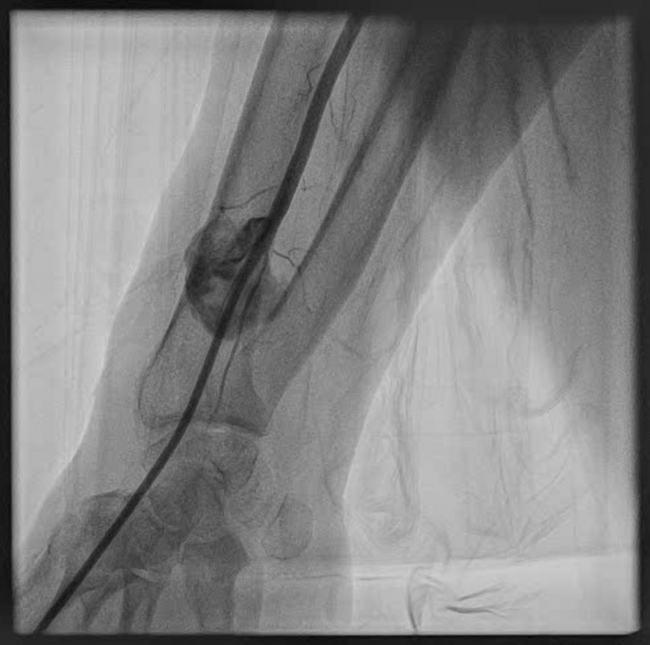

Because of the absence of injectable thrombin solution and the frail condition of the patient, it was decided to proceed with an endovascular approach. A 6F sheath was introduced in the distal radial artery (Figures 1 and 2, Video 1). Using a 6F Judkins catheter, a 0.014-inch guidewire was introduced inside the radial artery through the base of the RPA and distal to the brachial artery. A 3 x 24-mm polytetrafluoroethylene-covered stent was deployed initially, but with residual leak (Figure 3, Video 2). A second 3 x 18-mm covered stent was deployed, with minimal contrast flow inside the RPA. Final post-dilatation was performed with a 3.5 x 15-mm noncompliant balloon, with no residual flow inside the pseudoaneurysm. (Figure 4, Videos 3 and 4).